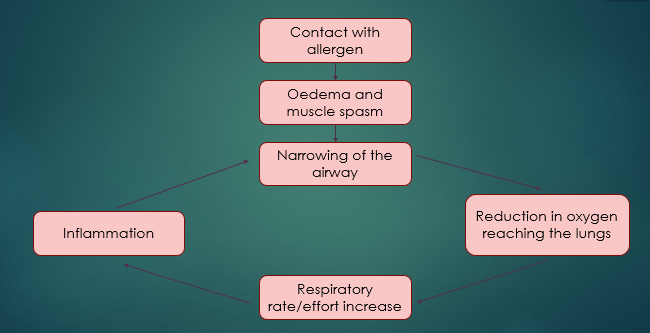

Anaphylaxis

Contact with allergen

Oedema and muscle spasm

Narrowing of the airway

Inflammation OR Reduction in oxygen reaching the lungs

Respiratory rate/effort increases

What is anaphylaxis?

A severe allergic reaction, body reacts, so becomes hypersensitive to a foreign substance

Patient has contact with the allergen - this is usually inhalation but can be caused by something else, such as a wasp/bee sting or blood transfusion reaction

It is in serve cases that we get respiratory distress

After the patient has come into contact with the allergen, Oedema occurs ..

Swelling and muscle spasm

This then causes a narrowing of the airway, so less o2 gets into the body

That’s what compensatory mechanisms kick in = increase respiration effort and rate, but this causes more inflammation and more narrowing

Becomes a vicious cycle of the body trying to correct it but the compensatory mechanisms are increasing the inflammatory response